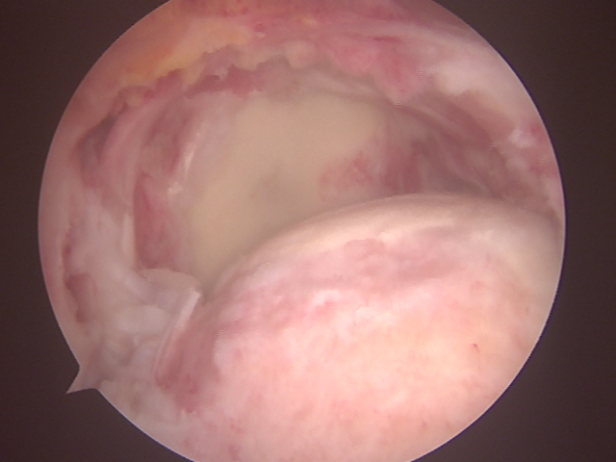

由于巨大肩袖撕裂手术难度大, 对缝合及重建的技术要求高,需要扎实的手术经验及操作技术才能完成。手术中手术团队默契配合,在关节镜下经充分松解后行肩袖修补,手术顺利完成,患者现恢复情况良好。